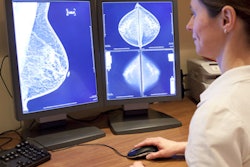

An artificial intelligence (AI) algorithm could obviate the need for a second radiologist to review a screening mammogram in more than four out of five exams performed for a national breast cancer screening program, according to a presentation on Monday morning at the virtual RSNA 2020 meeting.

A team of researchers led by Dr. Nisha Sharma of Leeds Teaching Hospitals NHS Trust in the U.K. simulated the use of AI as a second reader by retrospectively applying an AI algorithm to over 40,000 screening mammograms and then comparing the software's results with that of the initial radiologist interpretation. They found that over 80% of the exams could have been accurately categorized as either normal or abnormal without requiring any additional interpretation.

"Our study shows that an AI algorithm is a viable option to replace the second human reader in the double reading of screening mammograms," Sharma said.